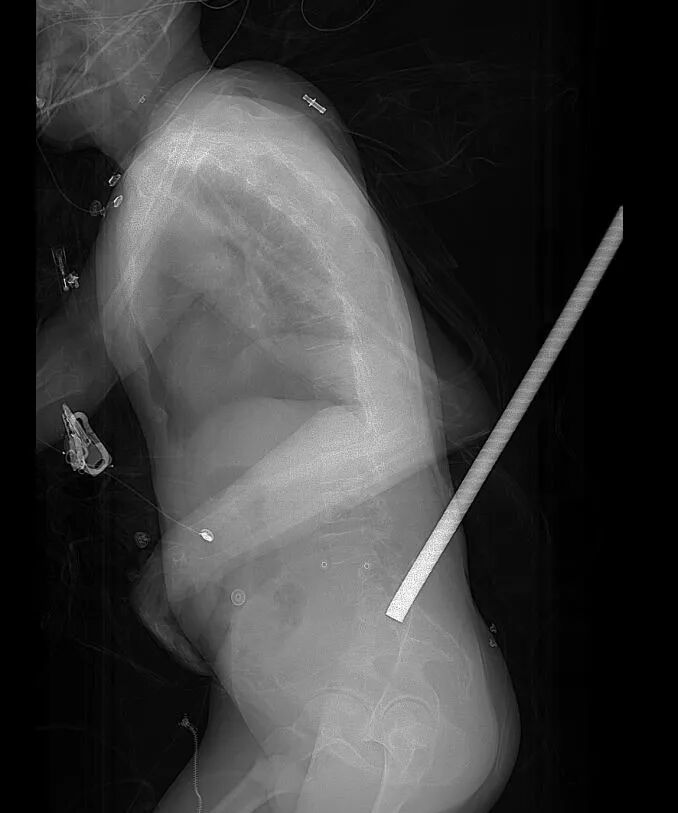

“钢筋刺入伤患者马上到,情况紧急!”12月3日,温岭市第一人民医院急诊室的应急铃声突然响起。创伤中心团队的医护人员迅速备齐抢救设备,相关科室人员同步集结,一场与时间赛跑的生命救援提前拉开序幕。据悉,一名工人作业时突发意外,被一根3米长的钢筋从后背刺入。

考虑到长钢筋不便转运,现场救援人员紧急将外露部分切割缩短,处理妥当后患者被火速送医。经检查,钢筋残留体外部分42厘米,体内嵌入长度约十几厘米。

“伤者到院时意识尚清,但钢筋刺入位置刚好对准腰椎四五节至骶骨区域,这是脊柱神经密集的‘生命地带’。”急诊医学科副主任蔡建华介绍13时57分接到120院前预警后,医院创伤中心10分钟内就完成了患者建档,急诊医学科、创伤骨科、脊柱外科、普外科、泌尿科等多个相关科室人员已全部集结到抢救室待命,同时还远程指导120救援人员做好现场处置。

经过20分钟的紧急处置稳定病情后,患者被迅速送往CT室进行检查。而多学科专家早已在CT室等候,随即启动MDT会诊,快速明确钢筋未伤及关键脏器的诊断,敲定了手术方案。

会诊结束后,患者直接从CT室转运至手术室,麻醉手术室团队早已准备好,实现无缝衔接。手术由脊柱外科张文斌主任医师、马子平副主任医师主刀,外科医生待命随时支援,团队先将42厘米长的钢筋完整取出,再细致开展清创与脊柱修复工作。整个手术衔接有序,最终顺利完成,患者术后被转入EICU,目前生命体征平稳。